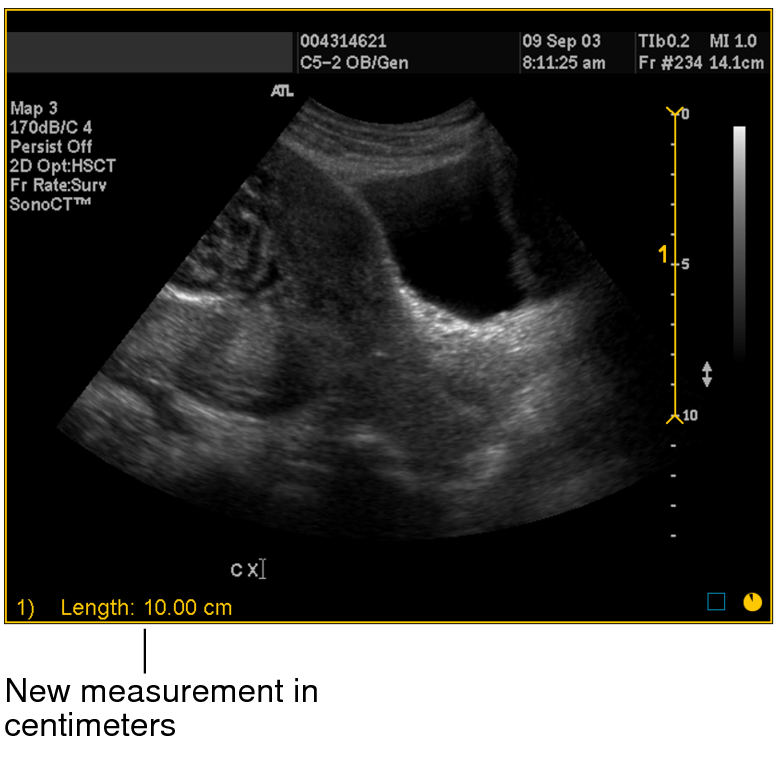

For example, in step 3 you can see that the drawn line corresponds to a length of 10 centimeters on the scale.

New measurement